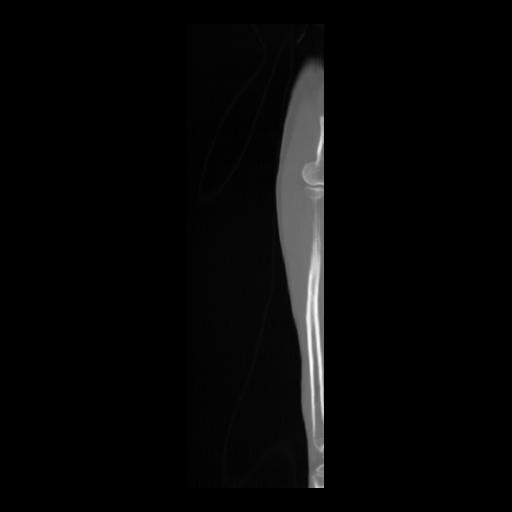

36 CUERPO,CE,Sagittal,3.000,CUERPO,Sagittal,